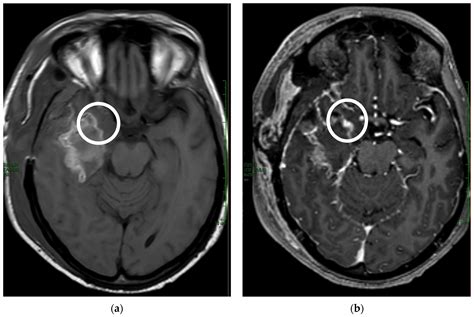

The primary reason for using a contrast agent is to improve the tissue contrast of the images produced. While an MRI is excellent at distinguishing between different types of soft tissues, some pathological conditions, such as tumors or infections, can blend into the surrounding healthy tissue. When a contrast medium is introduced into your bloodstream, it circulates through the body and accumulates in areas with increased blood flow or abnormal permeability. This results in a "brighter" or more distinct signal on the scan, allowing the imaging specialist to pinpoint the exact location and extent of a condition.